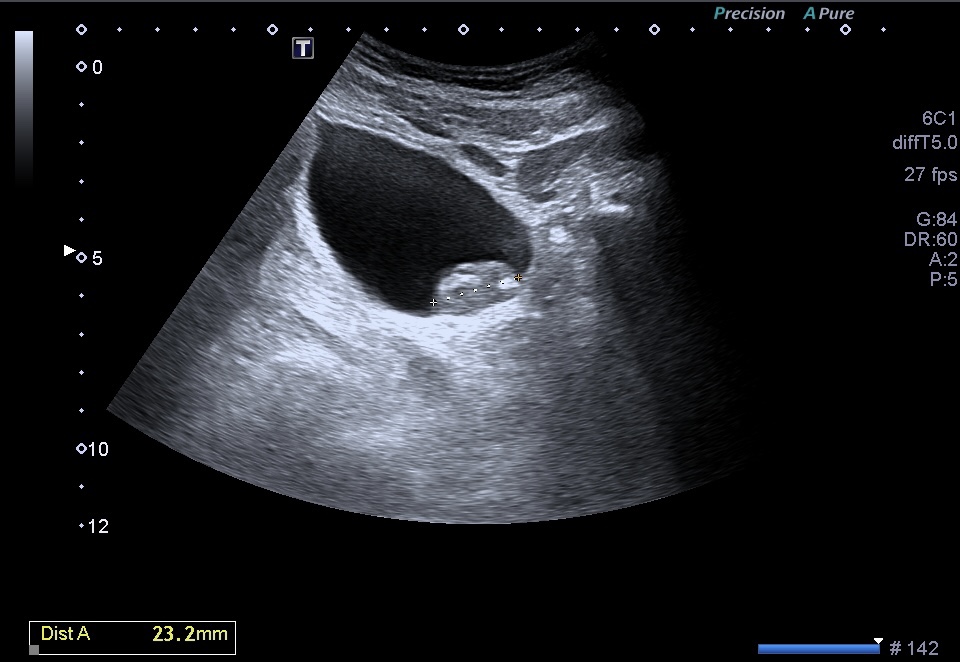

Al realizar una ecografía reno vesical, los hallazgos ecográficos típicos del urotelioma incluyen la visualización de una masa sólida en la vejiga.

Esta masa puede presentar una apariencia heterogénea, con áreas hipoecoicas (menos ecogénicas) y áreas hiperecoicas (más ecogénicas) en relación con el tejido circundante. Además, puede observarse un crecimiento intraluminal, lo que significa que la masa se proyecta hacia el interior de la vejiga.

- Contornos: Los contornos de la masa pueden ser irregulares y asimétricos. Pueden observarse proyecciones intraluminales, lo que indica que la masa se extiende hacia el interior de la vejiga.

- Tamaño: El tamaño de un urotelioma puede variar desde pequeñas lesiones hasta masas más grandes que ocupan una parte significativa de la vejiga.

- Estructura interna: La estructura interna del urotelioma puede ser heterogénea debido a la presencia de áreas de necrosis o hemorragia. Estas áreas pueden ser identificadas por su apariencia hipoecoica o hiperecoica respectivamente.También calcificiones…como es el caso que nos ocupa hoy.